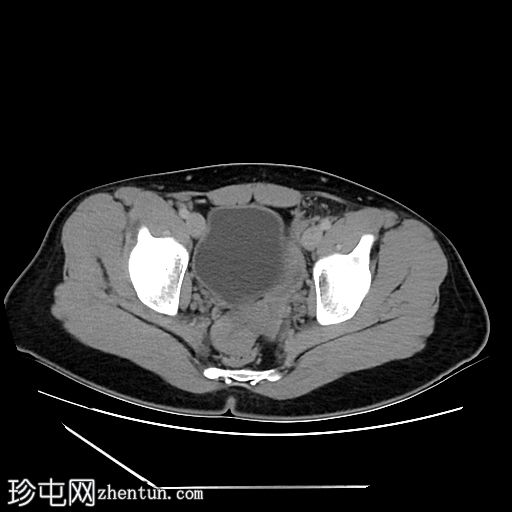

轴位增强扫描

门静脉期

阴茎:发育良好。阴茎海绵体和尿道海绵体均存在。

阴囊:双侧均存在,但空虚。

盆腔左侧可见一形态良好的子宫样结构(57 x 17毫米),开口于前列腺尿道。

右侧睾丸位于盆腔右侧,膀胱与直肠之间。大小:56 x 29 毫米。

左侧睾丸位于盆腔中线左侧,膀胱上方,子宫底旁。该结构附着于从左侧腹股沟管延伸出的索状结构上。大小:38 x 22 毫米。

患者有双侧隐睾病史。CT和MRI图像显示发育良好的子宫和两个睾丸,均位于盆腔内。子宫内膜腔开口于前列腺尿道。